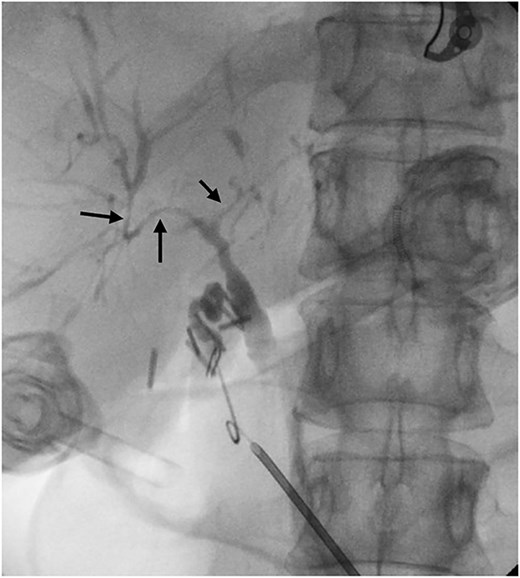

Six months after surveillance imaging, she was presented with ongoing abdominal pain. Liver function tests (LFTs) and Ca 19–9 remained normal at this time. A repeat abdominal US demonstrated an irregular gallbladder wall with thickening up to 5 mm and two stable gallbladder polyps, the largest measuring 7 × 8 mm (Fig. 2). Due to ongoing symptoms and changes on imaging, a laparoscopic cholecystectomy with intraoperative cholangiogram was performed without complication. At the time of surgery, the gallbladder was noted to have an area of wall thickening thought to be a Phrygian cap. The operative cholangiogram was consistent with PSC, with narrowed intrahepatic ducts observed (Fig. 3).

Preoperative ultrasound showing gallbladder polyp and wall thickening.